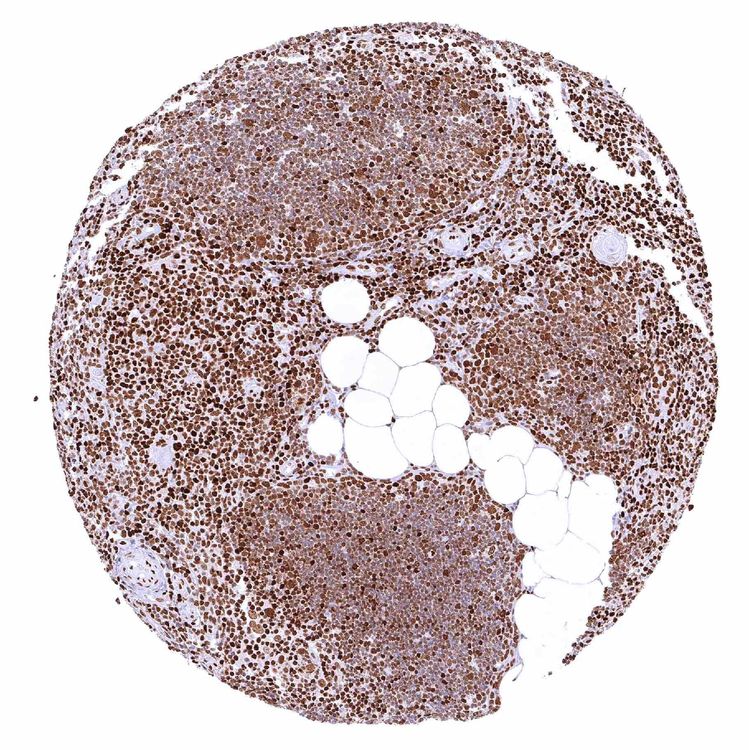

Bone marrow